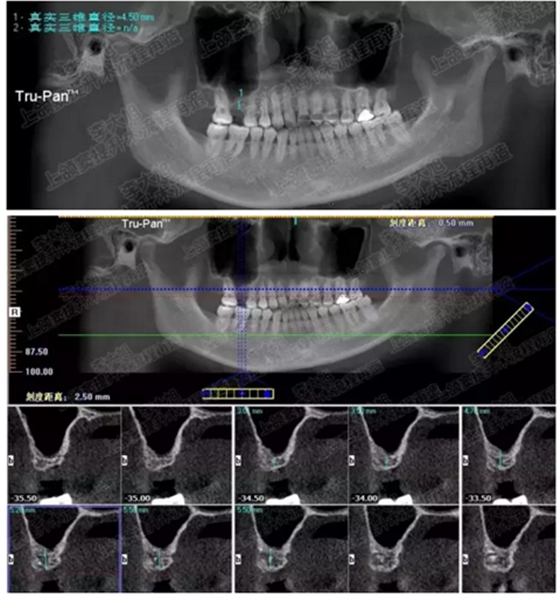

病例二

剩余骨量2mm

003.png

提升10mm

004.png

病例三

剩余骨量3mm

005.png

006.png

病例四

剩余骨量2mm-5mm且存在斜形竇底

007.png

提升8mm

008.png

009.png